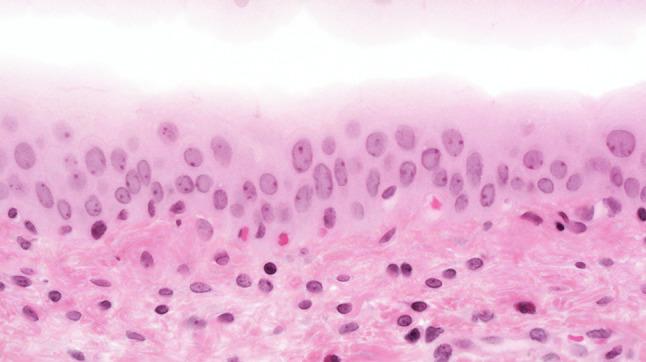

The morphology of experimentally induced urinary bladder precancerous lesions has been differentially interpreted in the literature. Here, we aimed to describe the development of precancerous lesions of the urothelium histologically and by DNA cytophotometric analysis.

We induced precancerous lesions of the urothelium in 60 Wistar rats with 0.05 % N-butyl-N-(4-hydroxybutyl)nitrosamine (BBN) solution as drinking water. After exposure for 2-20 weeks, each animal received tap water for 2 weeks. Subsequently, six animals were killed every 2 weeks, and urothelia of three urinary bladders per time point were examined by DNA cytophotometry of smear preparations. An additional three urinary bladders were processed for histological analysis.

Over 20 weeks, BBN exposure led to a significant difference between the control group and most of the BBN-exposed 2-week groups and to differences between most of these time point groups. After week 4, this difference included a higher proportion of cells with increased nuclear DNA content. At the end of the experiment, DNA cytophotometric values of the urothelium in experimental rats corresponded to those of poorly differentiated urothelial carcinomas.

Biologically significant stages of precancerous lesions were already detectable after 4 weeks of BBN exposure, considerably earlier than previously described in the literature.